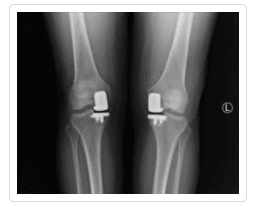

Knee X-ray Gallery

Please visit our knee x-ray gallery to see more images of knees affected by osteoarthritis.